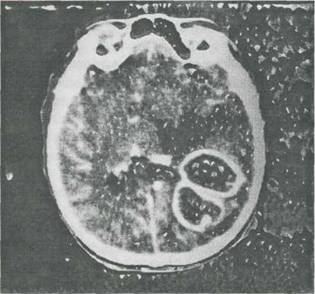

Fig. 9-12. Abcese cerebrale la un copil cu tetralogie Fallot. Tomografia computerizata cerebrala (colectia Prof.dr.serban Georgescu) evidentiaza doua abcese ^situate n lobul parietal drept; edem perilezional important (zona cu densitate redusa aflata deasupra abceselor); deplasarea sistemului ventricular (prin mpingere).